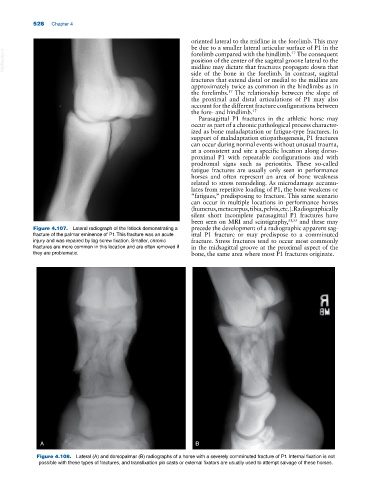

Figure 4.107. Lateral radiograph of the fetlock demonstrating a precede the development of a radiographic apparent sag-

fracture of the palmar eminence of P1. This fracture was an acute ittal P1 fracture or may predispose to a comminuted

injury and was repaired by lag screw fixation. Smaller, chronic fracture. Stress fractures tend to occur most commonly

fractures are more common in this location and are often removed if in the midsagittal groove at the proximal aspect of the

they are problematic. bone, the same area where most P1 fractures originate.